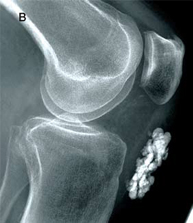

رادیوگرافی و سی تی اسکن

- بر حسب شرح حال و معاینه پزشک امکان دارد برای بررسی شکستگی استخوانی احتمالی یا دررفتگی زانو و گاهی برای بررسی برخی سطوح مفصلی یا مشاهده تغییرات تخریبی زانو ( آرتروز ) عکس رادیوگرافی ساده درخواست کند.

- بندرت پزشک برای بررسی دقیق شکستگی یا دررفتگی امکان دارد سی تی اسکن درخواست کند.

- هم سي تي اسکن و هم رادیوگرافی ساده برای بررسی شکستگی های عادی هستند اما هر دوی آنها در بررسی و ارزیابی بافت نرم مفصل که شامل رباطها, عضلات و تاندونها و منیسک ها می باشند ناتوان هستند.